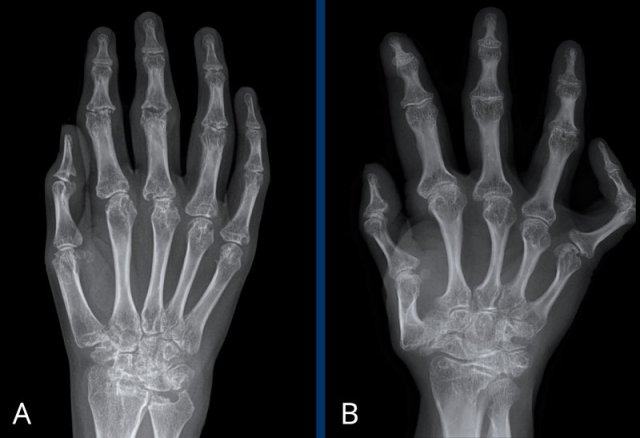

Erosive osteoarthritis in two patients Erosive osteoarthritis in two patients

A

Erosive changes of PIP 2-5 and DIP 3-5.

Typical gullwing deformity in DIP 3 (white arrow).

Ankylosing of PIP 4 (yellow arrow), which occurs in a late phase of the disease.

B

Joint space narrowing with central erosions. Gullwing deformity of PIP 2-4, DIP 2 and CMC-1 joint.

Ankylosing of DIP 3. Medial deviation of PIP 2.

Ball catcher view of the hands in a patient with erosive osteoarthritis.

There is bilateral extensive damage to the IP joints.

Note the symmetrical distribution and sparing of the MCP joints.

Typical gull-wing appearance of the DIP-joints, also known as seagull erosions or sawtooth appearance.

This is classically seen in erosive osteoarthritis, but has also been reported in psoriatic and rheumatoid arthritis.